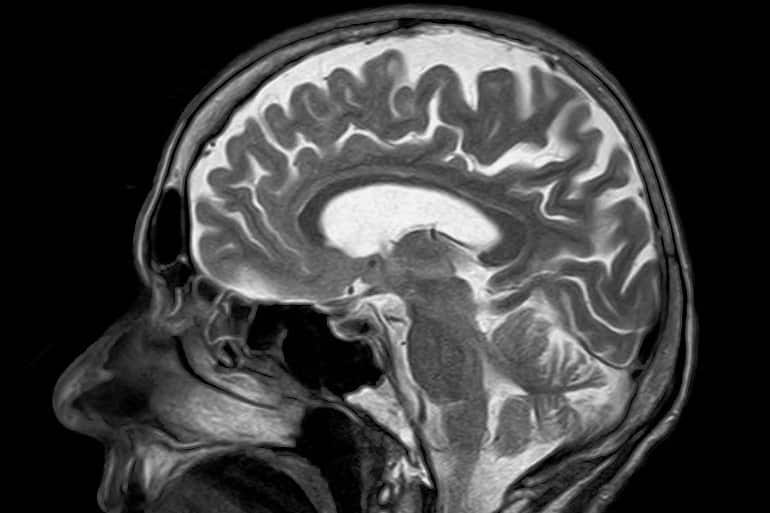

Strokes are a leading cause of poor quality of life or even death in Japan and the world over. Since its characterization, several researchers have been working tooth and nail to identify drug-accessible and effective therapeutic targets for this debilitating condition. One such region of interest for drug targets is the blood-brain barrier (BBB).

The BBB is a structure located around the brain, which prevents the entry of unnecessary circulating cells and biomolecules into the brain. The blood vessels in the BBB are coated with a distinct and protective layer of sugar, called the endothelial glycocalyx, which prevents their entry. However, in the event of a stroke, which results in the blockage or severance of blood vessels in the brain, studies have shown that this glycocalyx and, in turn, the integrity of the BBB, get compromised. In addition, damage to the blood vessels leads to neuronal death and the build-up of toxic byproducts like acrolein.